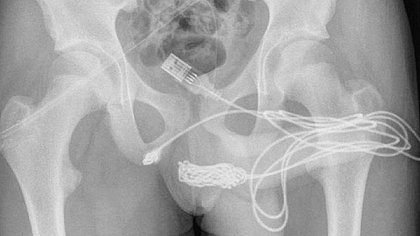

O jovem, que não teve o nome revelado, relatou aos médicos que inseriu um cabo USB, utilizado para carregar aparelhos celulares, na uretra para medir o comprimento do pênis. Ao perceber que havia prendido o cabo no membro, ele tentou removê-lo manualmente, mas acabou piorando a situação e prendendo as duas pontas do objeto na uretra.

O adolescente foi com a família ao hospital mais próximo, mas tentativas manuais ou endoscópicas de remoção não foram eficientes porque havia um nó no cabo USB.

Ele foi então encaminhado ao University College Hospital London, onde há tratamento especializado e cirurgias urológicas. Os médicos precisaram realizar uma uretrostomia penoescrotal, onde é feito um corte entre a genitália e o ânus do paciente. O cabo foi cortado e retirado através de um meato uretral externo.